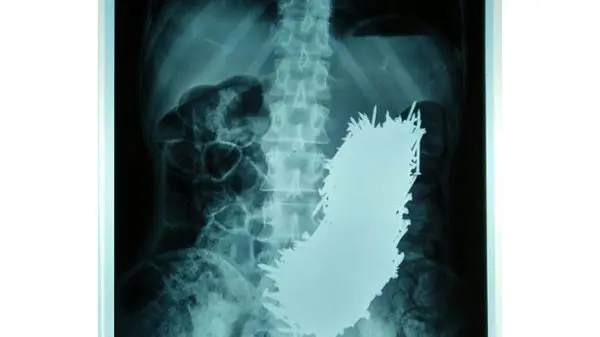

رکنا: پزشکان پس از عمل جراحی 600 میخ را از معده یک مرد 48 ساله خارج کردند.

این مرد به بیماری شدید اسکیزوفرنی مبتلا بوده و عادت شدیدی به خوردن نوشیدنی های گاز دار داشته است اما خانواده اش با دیدن میخ ها درون شکم وی شوکه شده اند.

دکتر «سیذارتا بیسواس» از کالج پزشکی در این باره گفت:« این مرد حدود دوماه از درد شکم رنج کشیده و به همین دلیل خانواده اش وی را به بیمارستان منتقل کرده اند. ما با انجام اسکن از شکم بیمار شوکه شدیم .خوشبختانه میخ ها معده را سوراخ نکرده وآسیب جدی به بیمار وارد نکرده بودند. برای بیرون کشیدن میخ ها پس از برش شکم از آهن ربا استفاده کردیم.»برای ورود به کانال تلگرام ما کلیک کنید.